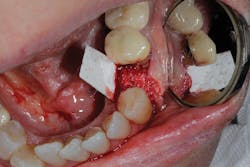

Because of this alveolar resorptive pattern after tooth extraction, bone grafting the extraction socket after tooth extraction procedures has become a solution that attempts to limit the amount of hard- and soft-tissue loss. There are many systematic reviews in the literature that compare the results of residual ridge dimension following tooth extraction after the use of a bone graft (with or without a membrane) versus extraction alone without grafting.7

• site development to increase hard and soft tissue for pontic sites in fixed bridge prosthetics (figures 9–14);• correcting bone defects impinging upon anatomical structures after tooth extraction, such as oroantral communication (figure 18); and